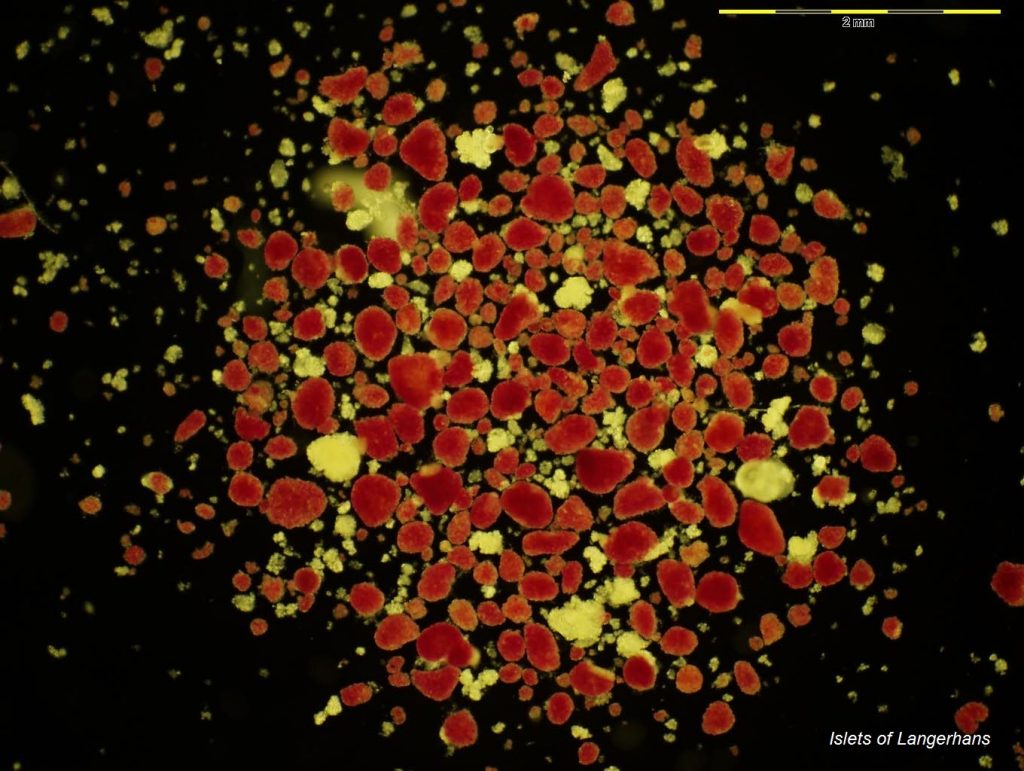

Islet isolation service

As a multidisciplinary team, we are of the few UK centres to offer total pancreatectomy islet isolation autologous transplantation as a clinical service.

The cell, gene and tissue laboratory isolate insulin-producing islet cells from pancreatic tissue, which are then transplanted back into the patient, reducing the dependency on insulin-based treatments post-surgery.